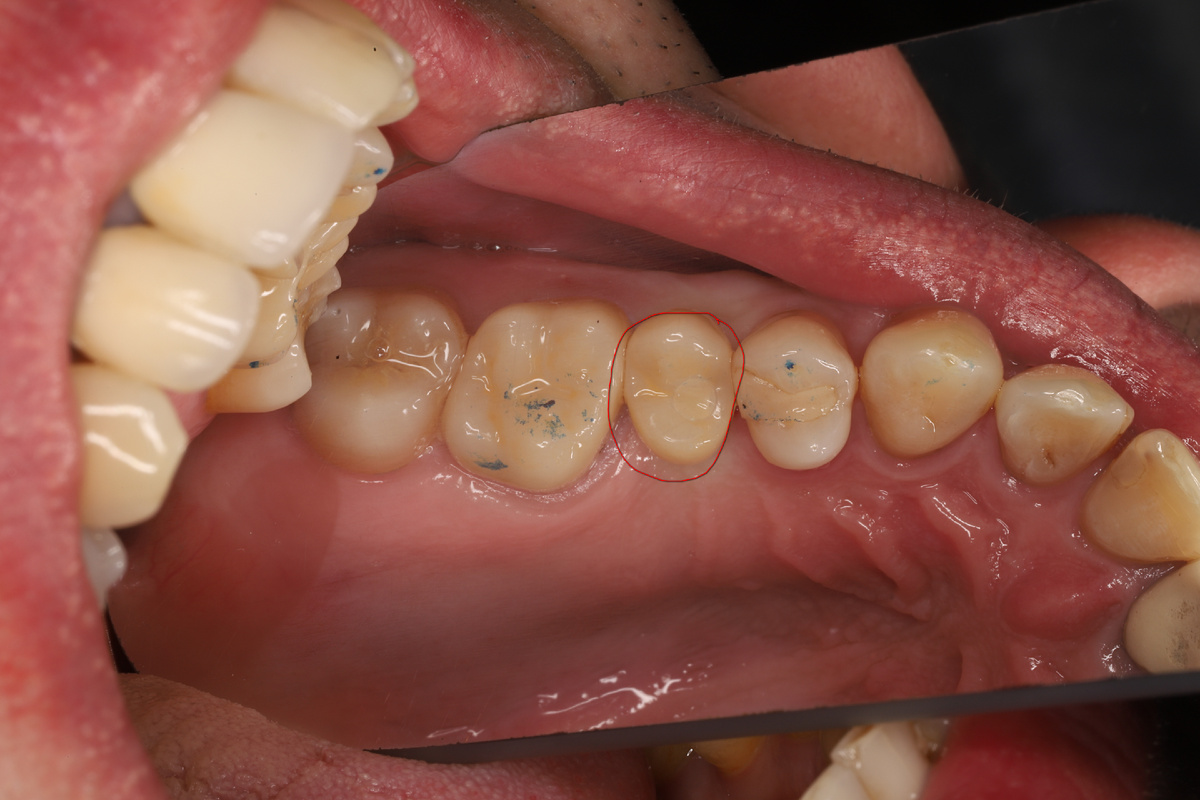

Так выглядит мостовидный протез, установленный на обточенные зубы. Фото взято из сети интернет.